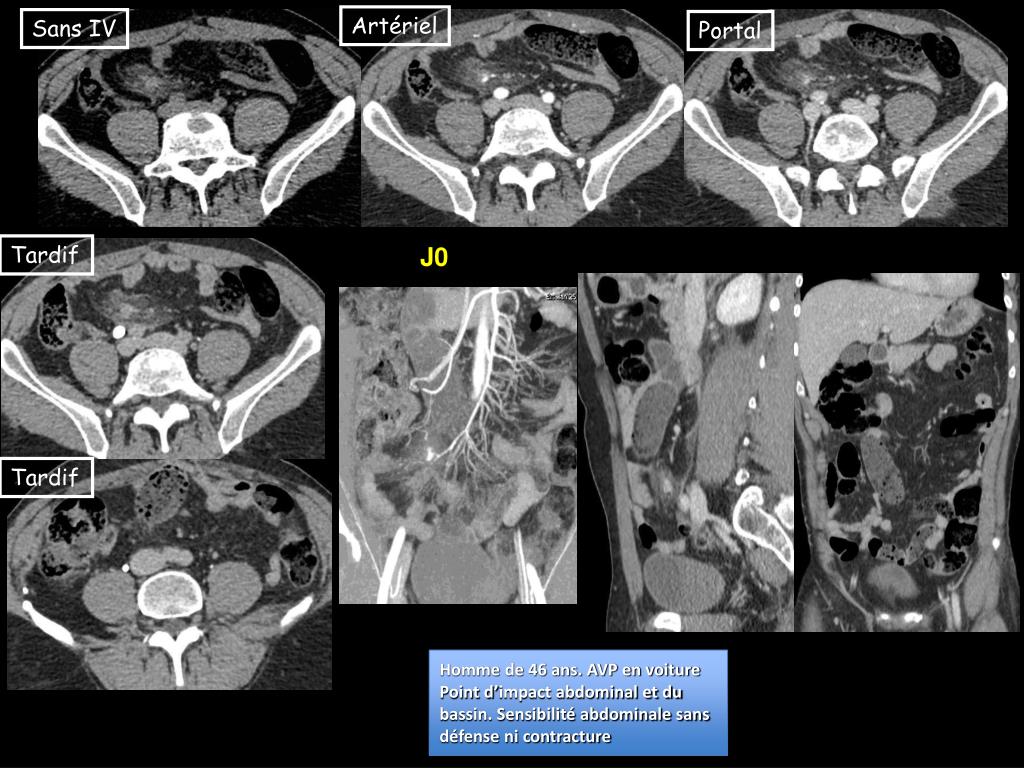

36. Artériel Sans IV Portal Tardif J0 Tardif Homme de 46 ans. AVP en voiture Point d’impact abdominal et du bassin. Sensibilité abdominale sans défense ni contracture

37. J1 Régression des douleurs, transit spontané. Retour à domicile à J4. Plaie vasculaire post-traumatique d’une branche de l’artère mésentérique inférieure, sans saignement actif, responsabled’un début d’ischémie grêlique focale, réversible.